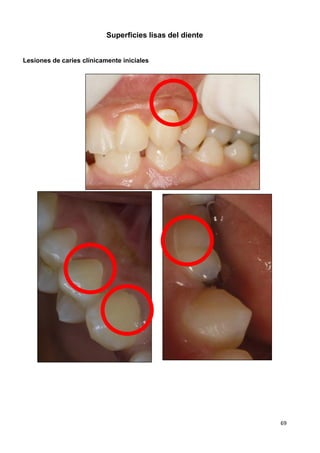

recomendado para niños ≤ 6 años. (SIGN 1---)

67,76

MNO: Sellantes a base

de resina/ionómero de

vidrio (SIGN 1+ / 1---)

65,79

MNO: Sellantes a base de

resina /infiltrantes

(SIGN 2--) 87

MNO: Higiene oral con crema dental fluorada (1000 ppm) cuando